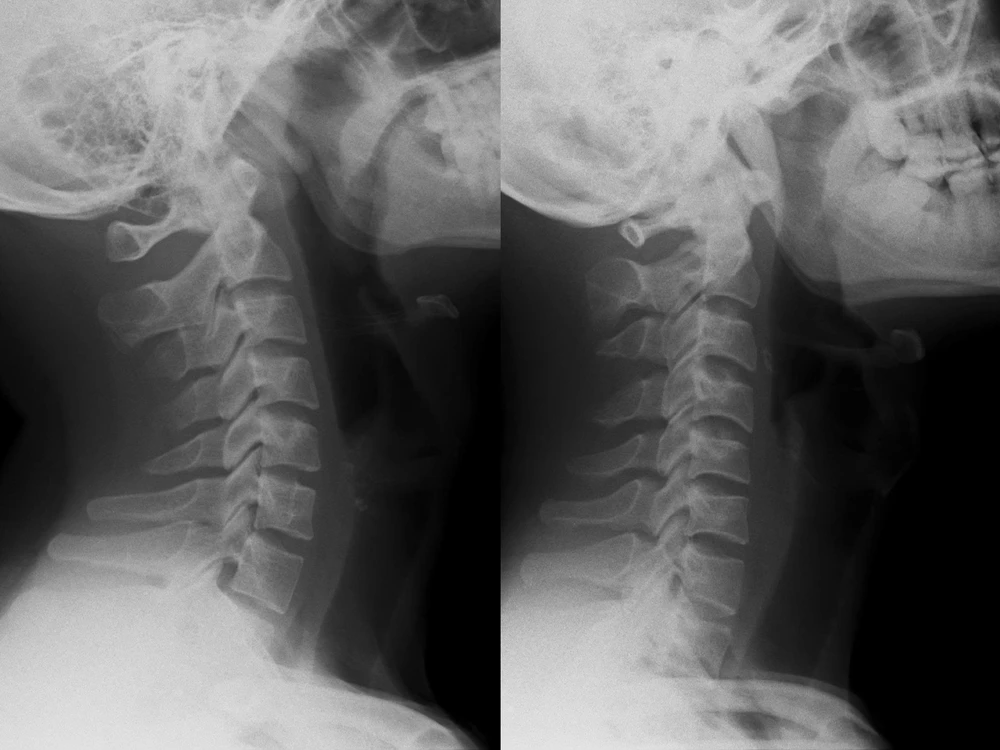

Sau khi thăm khám và chỉ định chụp X-quang cột sống cổ thẳng nghiêng, kết quả cho thấy cột sống cổ bệnh nhân mất hoàn toàn độ cong sinh lý (còn gọi là cổ thẳng), khiến các đốt sống cổ gần như xếp dọc thay vì có độ ưỡn ra trước như bình thường.

Hình ảnh X-quang cột sống cổ bình thường (trái) và mất đường cong sinh lý cột sống cổ (phải). Ảnh: BVCC